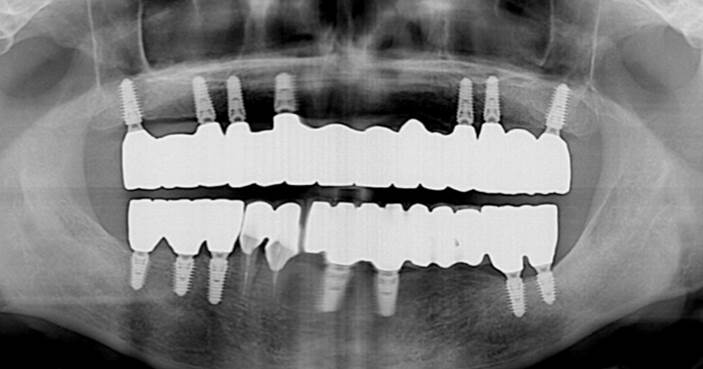

“AnyRidge ensures long-term biological stability

& functionality even in

full-mouth rehabilitation case. ”

Clinical case: Full-mouth implants for mandibular & maxilla - restored using mixed prostheses

- Courtesy of Dr. Hyun Jun Kim, Korea -

Keywords

AnyRidge, full-mouth implants, mandibular, maxilla, edentulous, full mouth rehabilitation, Octa abutment, long-term clinical case, biological stability, Dr. Hyung Jun Kim

Products:

AnyRidge implant system